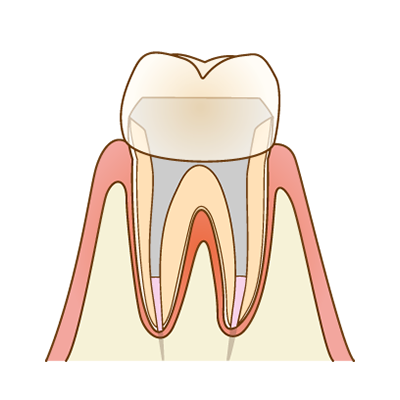

補綴修復(被せ物)

最後に、歯を守るための被せ物(クラウン)を装着します。被せ物は、見た目だけでなく、歯との適合精度が非常に重要です。マイクロスコープを用いて適合を確認し、細菌が入り込みにくい状態を目指します。

根管治療がうまくいっていても、被せ物の精度が低いと再発のリスクは高まります。当院では、根管治療から補綴修復までを一貫して精密に行うことを大切にしています。